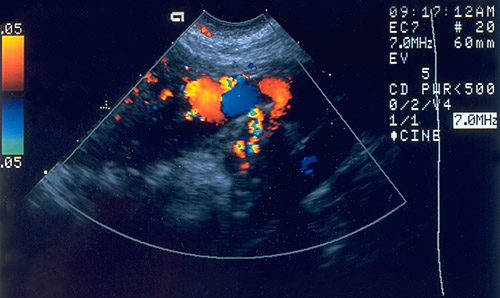

This endovaginal ultrasound of the uterus in the pelvis demonstrates an invasive mole in the region of abnormal vascularity extending into the myometrium.